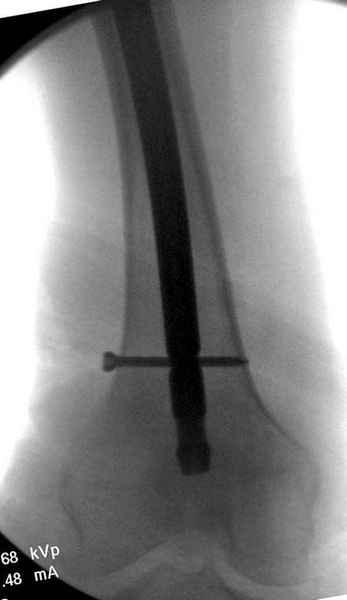

На второй день после выписки упал дома. Снимки приложены. Коллеги рекомендуют удаление шурупа и вытяжение. Что делать?

Правильно, ситуация изменилась, как говорят у нас теперь "different animal", надо решать проблему подвертельного перелома. При наличии различных вариантов фиксаторов, включая Страйкер Гамма 3, мы выбрали DePuy Antegrade Trachanteric Nail из-за многовариантности проксимальной фиксации и двойного изгиба. Вводится через вертел под 8 градусным углом, и есть достаточный передний диафизарный изгиб, предупреждающий пенетрацию дистального переднего кортекса.

Привет из солнечного Будапешта с Eurotrauma-2008. Да, замечательный пример. Получается, профилактику расхождения отломков шейки надо было проводить каким-то реконструкционным или проксимальным гвоздем, причем сразу длинной версией. Сейчас, наверно, так и надо бы сделать.

Убрать винты, каким-то джойстиком в вертельной области сделать репозицию шейки, фиксировать ее спицами, а дальше вправлять и фиксировать как вертельный перелом.